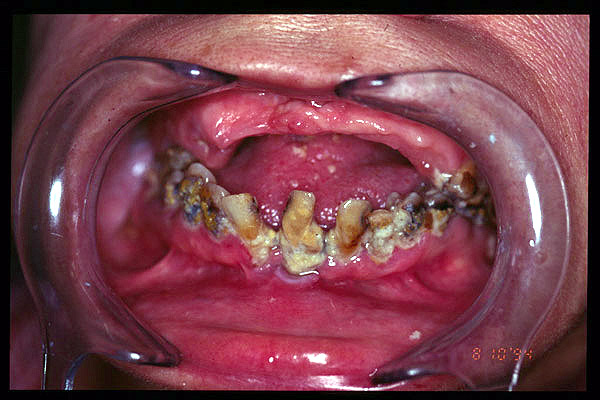

CM Caries, patología periodontal, desgaste.